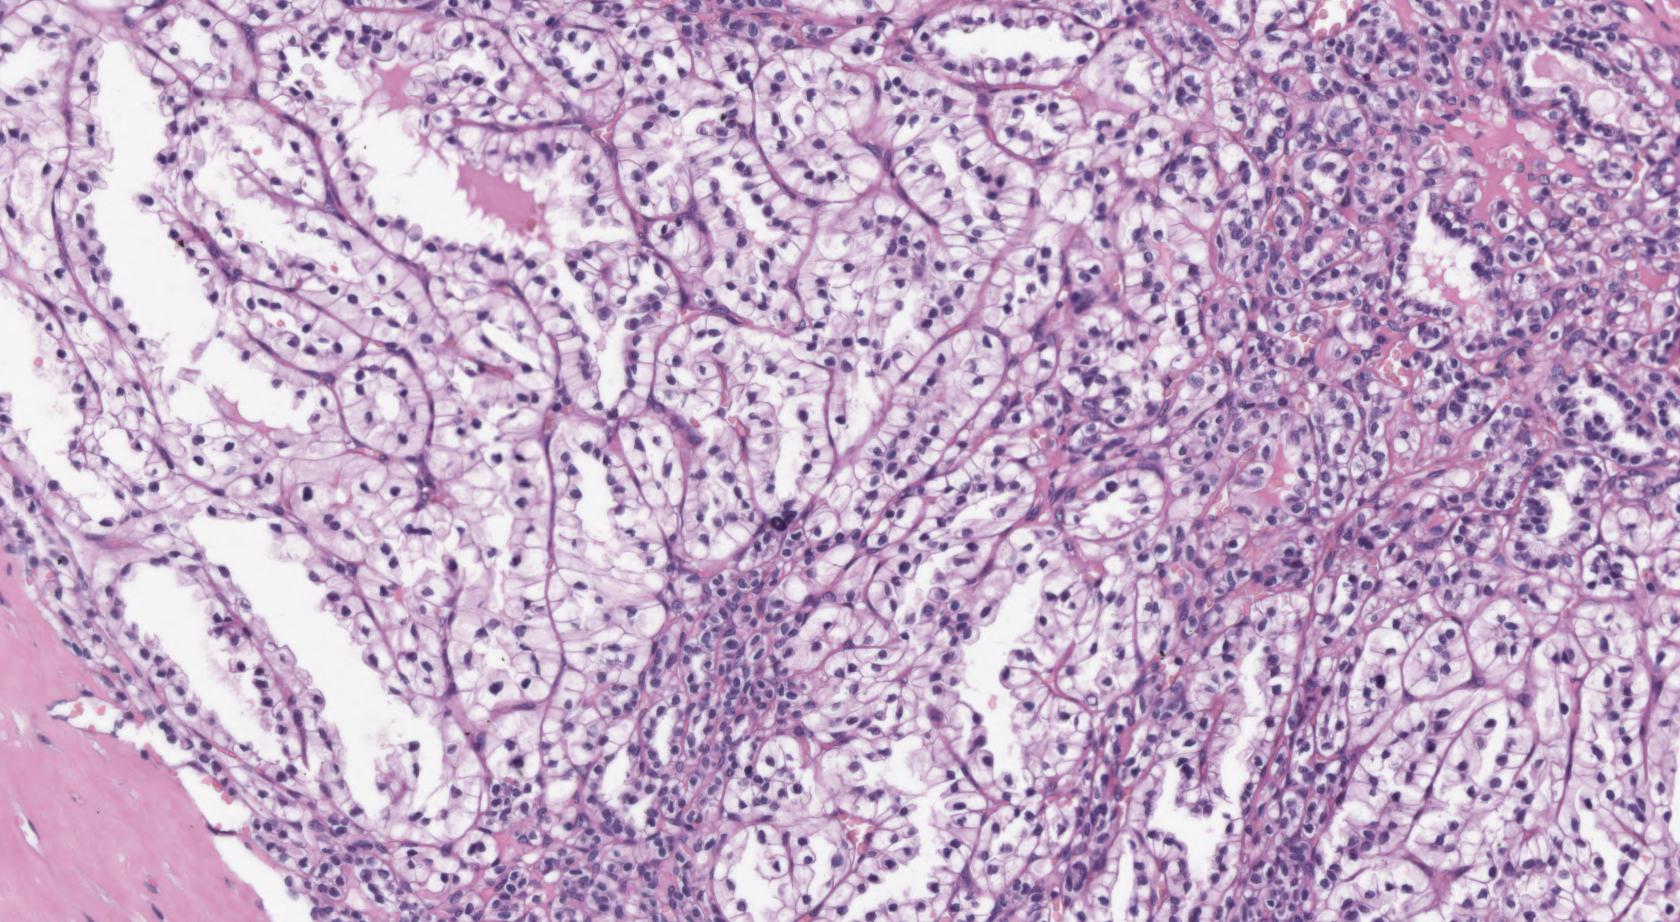

Consensus grade: Clear cell tubulopapillary RCC

A 55-years-old man underwent clinical attention for a nodule of 4 cm on the right kidney.

A tumour enucleation was performed.

The microscopic examination showed a tumour with tubulo-papillary architecture, composed of cells with clear cytoplasm and low-grade nuclei.